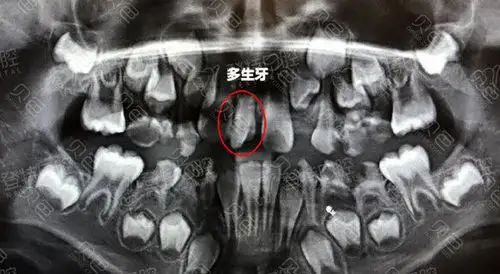

儿童多生牙ct拍摄图片

全景牙科 x 射线八岁儿童的问题不松动他的乳牙-持续乳牙

9岁10个月,右侧中切牙乳牙未换,右侧切牙已换